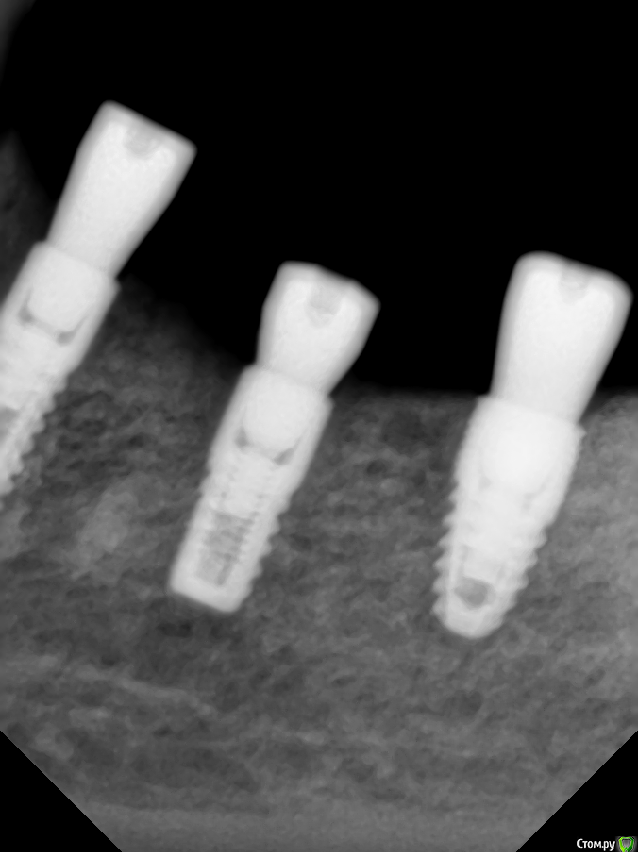

Sergiosse Опубликовано 4 декабря, 2019 Поделиться Опубликовано 4 декабря, 2019 Установил три импланта , средний вплотную к н.ч. каналу. После формирования ложа при зондировании перфора не было . на следующий день после операции онемение в области угла рта не проходит . Думал что из-за отёка. Сегодня пятый день. Изменений нет. Сильных болей нет , хотя пациентка принимает Кетонал. Пациентка сейчас в Москве , я я хочу попросить её чтобы она дошла до хирурга и на пару оборотов выкрутила средний имплант . вопрос Нужно ли это делать , как удостовериться, что это именно из—за импланта,сделать Кт? Отслойку лоскута делал осторожно,к выходу нерва не приближался , кровотечение и боли во время операции не было . Я думаю может быть медсестра (новенькая , неопытная )фарабефом придавила?=48001:тазеева2.png] Ссылка на комментарий

dok1 Опубликовано 4 декабря, 2019 Поделиться Опубликовано 4 декабря, 2019 Вообще по снимку как будто провалились слегка. Если это действительно так, то выкручивание большой пользы непринесёт 2 Ссылка на комментарий

Dmitry DK Опубликовано 8 декабря, 2019 Поделиться Опубликовано 8 декабря, 2019 Если вы все сделали по "инструкции" ( которая у вас на КТ ), наверняка имплантат оказался вплотную к каналу, но не думаю, что вы в него погрузились, но КТ нужно сделать для перестраховки.Скорее всего - фрезой залезли в канал ( он не обязательно должен кровить ), в таком случае выкручивание имплантата не поможет. Вопрос в том как сильно был поврежден сосудисто-нервный пучок, от этого будет зависеть динамика Ссылка на комментарий

Sergiosse Опубликовано 16 декабря, 2019 Автор Поделиться Опубликовано 16 декабря, 2019 В продолжение истории. Жалоб кроме, как на онемение нет. витамин В12 назначил. Думаю,продавил имплантом стенку канала,кагда давал торк. Через неделю увижу пациентку,какая дальнейшая тактика? Под нагрузкой от коронки не будет болей? странная верхняя стенка канала, с размытыми границами, остеопорз? Ссылка на комментарий

Irouil Опубликовано 17 декабря, 2019 Поделиться Опубликовано 17 декабря, 2019 ИМХО, не похоже, что продавили 2 Ссылка на комментарий

Dmitry DK Опубликовано 27 декабря, 2019 Поделиться Опубликовано 27 декабря, 2019 Винт не в канале, очевидно, что фрезой задели. Выкручивание ничего не даст ( на нерв не давит). Удалять на случай разборок... Зачем?... Если разбор реально будет, на КТ все видно. Не переживайте, все наверняка восстановится через месяца 4, последней фрезой до нижней стенки вы видимо не дошли Ссылка на комментарий